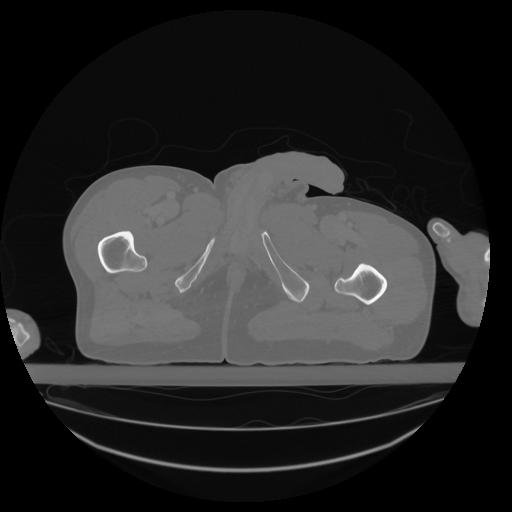

34 CUERPO,CE,Vol,1.0,CUERPO,,